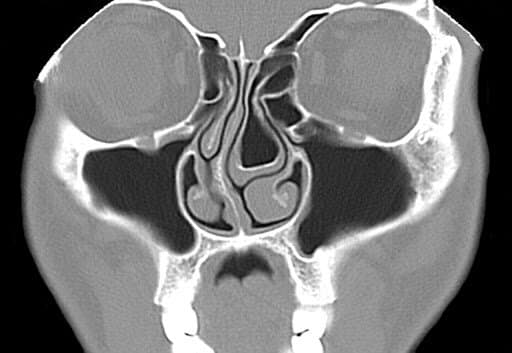

Seasonal sinus pain refers to inflammation, pressure, congestion, or discomfort in the sinus cavities that tends to arise or worsen during particular times of the year. This pain usually links to environmental changes such as pollen surges, shifts in humidity, temperature drops, or an increase in airborne irritants. These factors cause the delicate lining of your sinuses to swell and produce mucus, leading to symptoms like facial pressure, headaches, nasal stuffiness, and sometimes even tooth pain.

Each season brings environmental challenges that can negatively impact your sinuses. When triggers like pollen, dry air, or mold spores irritate the sensitive mucous membranes lining your sinus passages, swelling and mucus production tend to increase. This leads to congestion, facial pressure, and sometimes infections. Let’s explore the most common seasonal sinus pain triggers and how they affect you.